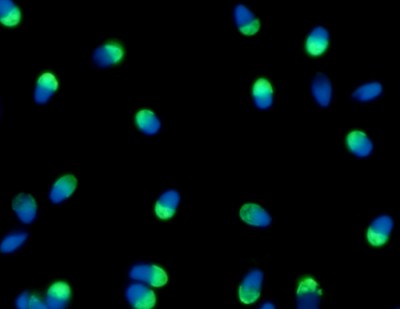

Implementan en la Argentina una novedosa técnica que selecciona los espermatozoides sanos , ya hubo más de cien nacimientos

El grupo de trabajo de la doctora Vanesa Rawe fue de los primeros en Argentina en implementar una novedosa tecnología llamada “Columnas de Anexinas V” que selecciona espermatozoides de buena calidad desde una muestra en...